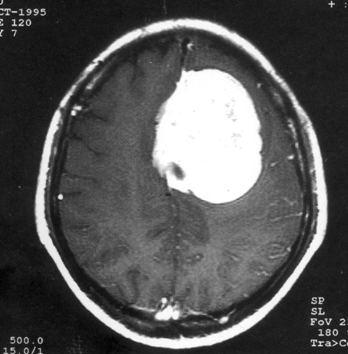

问题 病历摘要:??患者,男,40岁。发作性左下肢抽搐1年余,每次发作3~5分,每周发作1~2次。每次发作后感左下肢乏力,约半日后可自行恢复。既往身体健康。体检:神清,头顶部偏右有局限性骨性隆起(1.5×1.5cm),左鼻唇沟稍浅,伸舌居中。感觉、运动无明显异常。左浅反射减退,左下肢腱反射稍亢进,左Babinski征(-)。 术中下列哪些处理是错误的?提示:脑血管造影示上矢状窦中段闭塞,肿瘤有右脑膜中动脉和大脑前动脉分支供血。

选项 A.切皮前半小时给予抗生素 B.右顶开颅,切口至中线 C.电灼上矢状窦表面出血 D.对横跨在肿瘤表面的中央静脉电凝后切断 E.沿肿瘤和脑组织分界面以食指分离 F.连同肿瘤一起切除相连的矢状窦 G.切除受侵犯的硬膜,以人工脑膜修补 H.去除受侵犯的颅骨,以人工颅骨修补 I.术中静滴德巴金

答案 DE